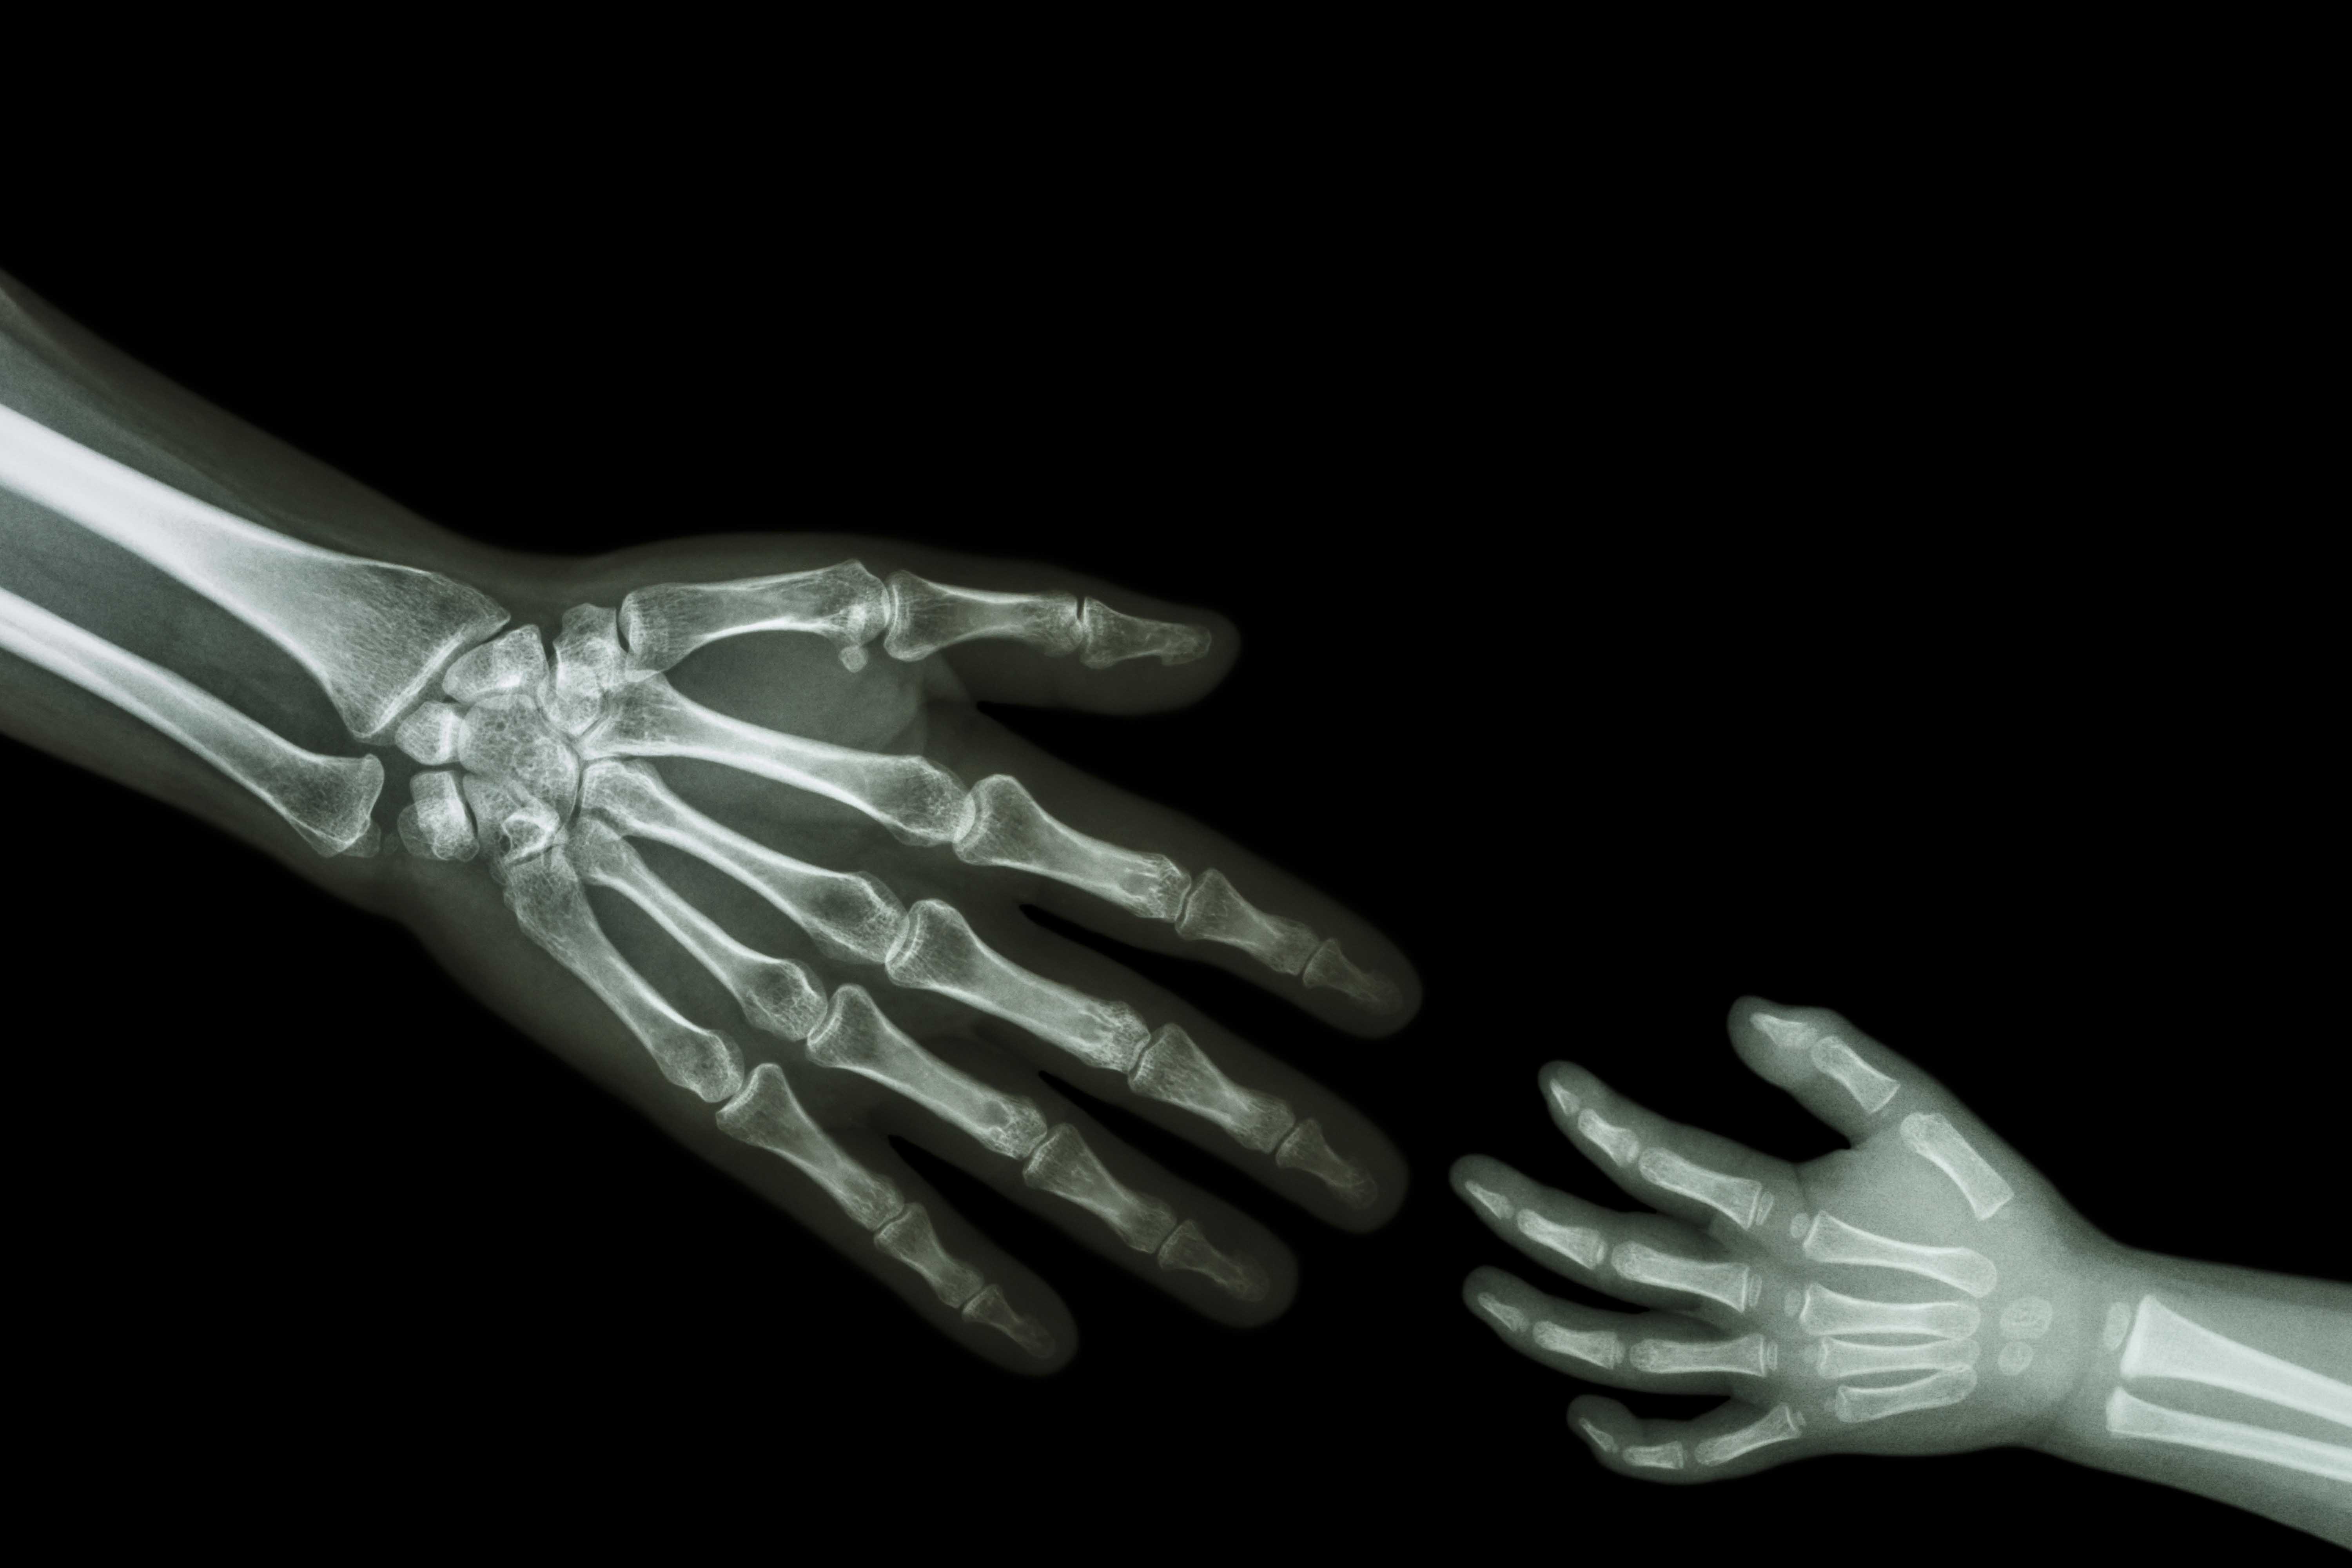

يهدف برنامج زمالة الأشعة التشخيصية لدى الأطفال والذي يمتد عامين إلى تزويد المتدربين بتعليم عالي المستوى في التصوير بالأشعة للأطفال. وتتميز بيئة عمل شعبة الأشعة التشخيصية للأطفال بالاستقلالية الكاملة مما يتيح للطبيب المتدرب فرصة فريدة للتعامل مع المرضى من الأطفال. ويتم التأكيد على جوانب الأمان في الأشعة والتسكين التباين وهي ذات أهمية خاصة للأطفال. ويتعلم الأطباء كيفية أداء وتفسير الدراسات بشكل سليم ويتضمن ذلك الأشعة فوق الصوتية، والمنظار الفلوري، والأشعة المقطعية، والرنين المغناطيسي والتصوير بالأشعة التقليدي. ويمثل الكم الكبير من الحالات قيمة مضافة، فضلاً عن التشكيلة المتنوعة من الأمراض الخلقية، و أمراض القلب و الأوعية الدموية والأورام والرعاية الحرجة والتي يتم التعامل معها في هذه المؤسسة.